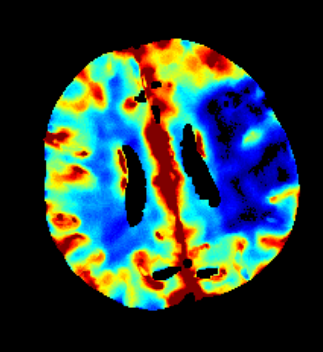

Des Weiteren ist mRay in der Lage eine Verarbeitung von Bildern durchzuführen und so Veränderungen bzw. Anomalien in Geweben zu finden, zu visualisieren und zu quantifizieren. Das Bildverarbeitungsmodul mRay VEOcore kann verwendet werden, um Bilder des Gehirns von Bildgebungsmodalitäten wie CT, Perfusions-CT oder MRT mit diffusionsgewichteter Auswertung (DWI) zu prozessieren. Als Ergebnis werden Kontrastveränderungen über die Zeit als farbige Perfusionskarten angezeigt, dies beinhaltet auch flussbasierte Parameter und Gewebeblutvolumen Berechnungen.

Die Perfusionsanalyse von Aufnahmen des Gehirns ermöglicht die Darstellung und Quantifizierung von minderdurchblutetem Gewebe (Penumbra), nicht-durchblutetem Gewebe (Kerngewebe) und dem Mismatch-Ratio zwischen den beiden Werten. Die berechneten Werte können der Unterstützung bei einer Entscheidungsfindung dienen, die auf der Beurteilung des Ausmaßes der Schädigung von Geweben basiert.